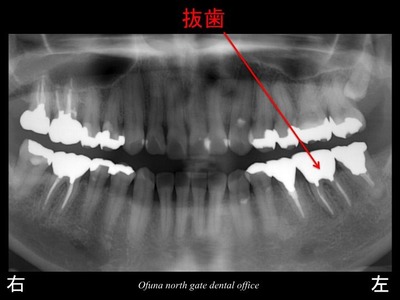

下顎左側の奥から2番目の歯は、抜歯となります。

以下は、抜歯後です。

この患者様は、神経がない歯が非常に多いことが分かります。

以下が抜歯後です。

この方も神経のない歯が多いですね。

これも保存が難しいため、抜歯となりました。

以下が抜歯後です。